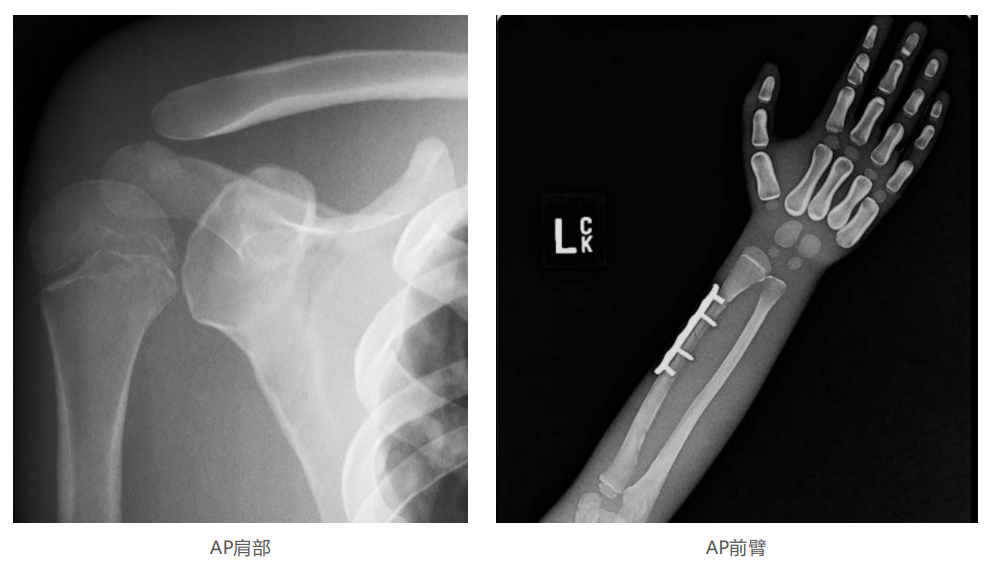

仿真人體模體旨在幫助教學(xué)和提高患者對(duì)體位、準(zhǔn)直和解剖學(xué)的理解,其廣泛的特點(diǎn)有助于安全、高質(zhì)量的人體影像學(xué)的有效指導(dǎo)。

模體的大小和結(jié)構(gòu)都代表了人體模體,使其便攜和易于定位。包括頭、胳膊和腿在內(nèi)的整個(gè)身體。該系列包括六個(gè)部分的模體可單獨(dú)或作為一個(gè)完整的集合。

右肢有伸直或彎曲兩種配置。左臂和左腿可選伴有或不伴有內(nèi)嵌骨折。

骨折版本包含最常見(jiàn)的人體骨折類型 ,包括脛骨扣帶骨折和腓骨普通骨折;

第一跖骨骨折;橈骨切開復(fù)位骨折 ,第二中間趾骨常見(jiàn)骨折。組件由適當(dāng)?shù)木郯滨ズ铜h(huán)氧材料制成,模擬人體組織的X射線衰減特性,用于診斷和治療能量范圍(50 keV - 25 MeV) 。 材料經(jīng)久耐用 ,耐沖擊,適合連續(xù)搬運(yùn)。透明的軟組織有助于解剖標(biāo)志的視覺(jué)指示。